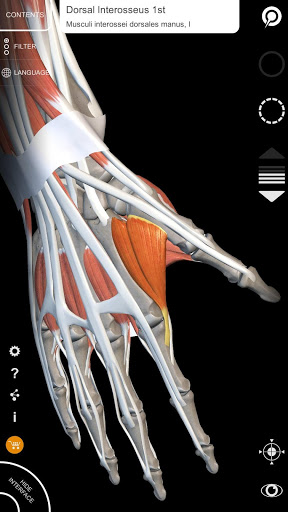

• تصور العضلات من خلال مستويات الطبقات من الطبقات السطحية إلى الأعمق

• من خلال تحديد نموذج أو دبوس، يظهر المصطلح التشريحي ذي الصلة

• وصف العضلات: الأصل والإدخال والتعصيب والعمل